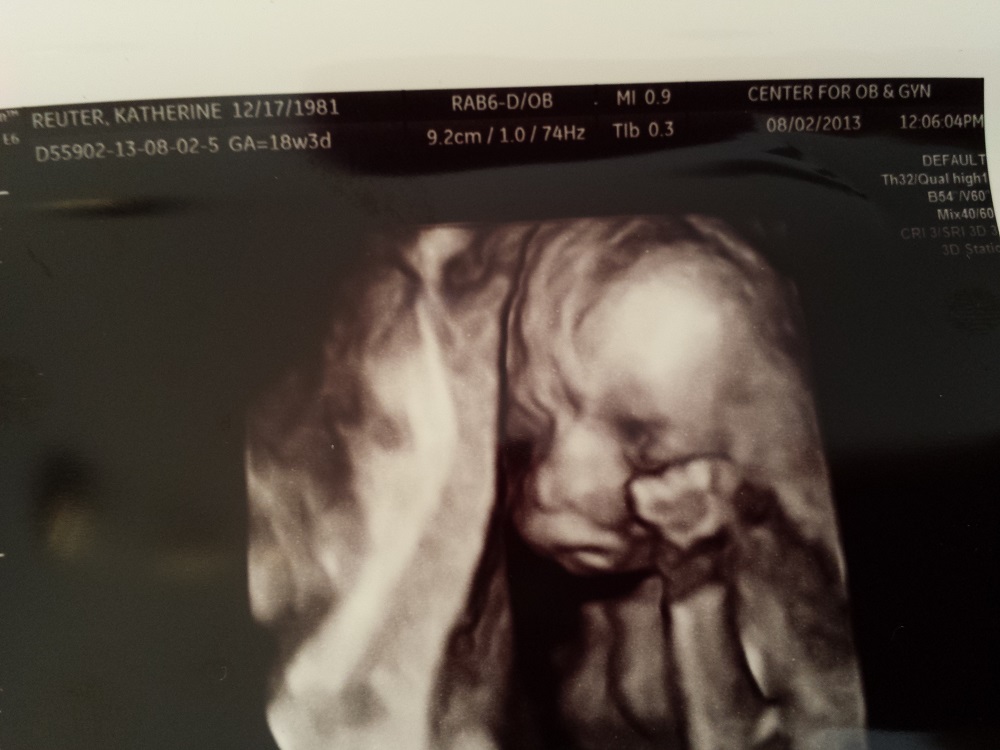

I promise this is the last thread I am posting then my OCD with this will stop hehe You guys are awesome for helping! Since I don't have any good nub shots can you take a look at the shape of the skull and make your best guess! xo

Attachment 12863